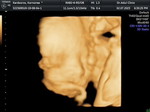

15วีคซาวด์เห็นเพศไหมครับ

เห็นได้ค่ะ ถ้าน้องยอมให้เห็น บางทีอยู่ในท่าที่ไม่เห็น ของเราตอน 14วีคไม่ยอมเลย มาเห็นตอน 18วีค แต่เราตรวจ NIPT ตั้งแต่ไตรมาสแรกแล้ว เลยรู้เพศมาก่อนค่ะ 😂🤣